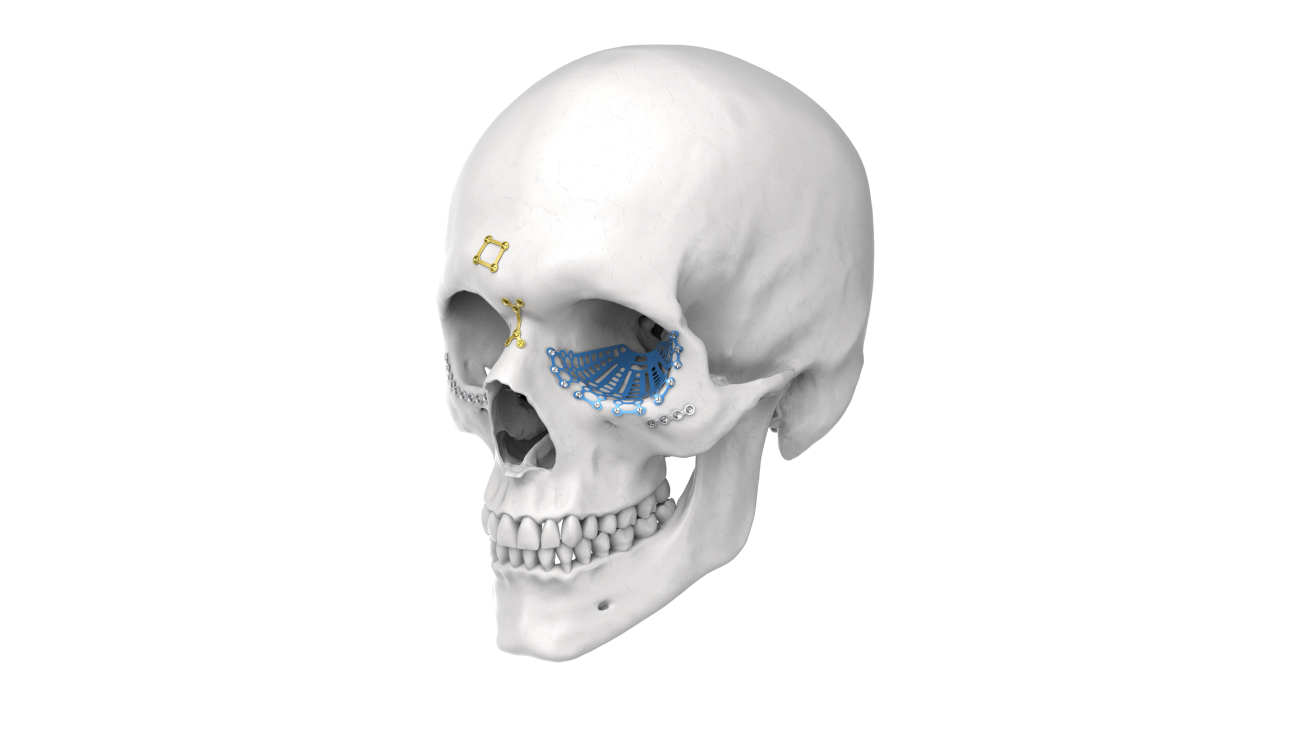

OMF Custom-Made PSI

Our OMF Custom-Made Patient-Specific Implants (PSI) are designed using advanced 3D planning and manufacturing technologies to achieve precise anatomical fit and superior reconstructive outcomes. These implants are ideal for complex facial and mandibular reconstructions.